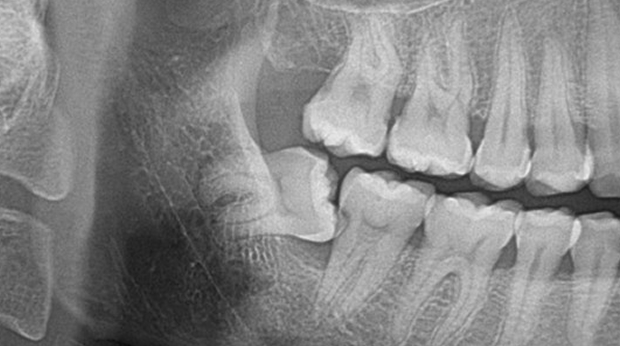

매복 사랑니 발치

고난도 수술 진료

임플란트와 사랑니 발치는 외과적 시술로 잇몸을 절개하는 외과적 시술은

짧으면 짧을 수록 시술 후 붓기와 통증이 최소화됩니다.

치과의사 경력 14년차 구강외과 전문의가 빠르고 안전하게, 아프지 않게 수술해 드립니다.